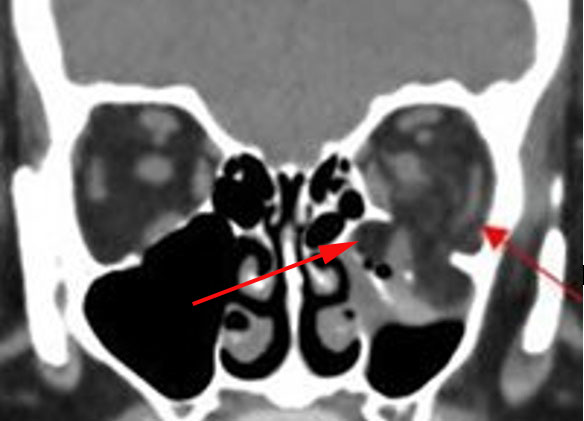

There is evidence of herniated intra-orbital fat. [Yes/No]

The extraocular muscles are swollen, infiltrated or herniated into a fracture site. [Yes/No]

The mesial naso-orbito-ethmoid complex is fractured. Specifically, there is bony injury of the nasal bones or the frontal process of the maxilla and the medial walls of the orbit are abnormal. [Yes/No]